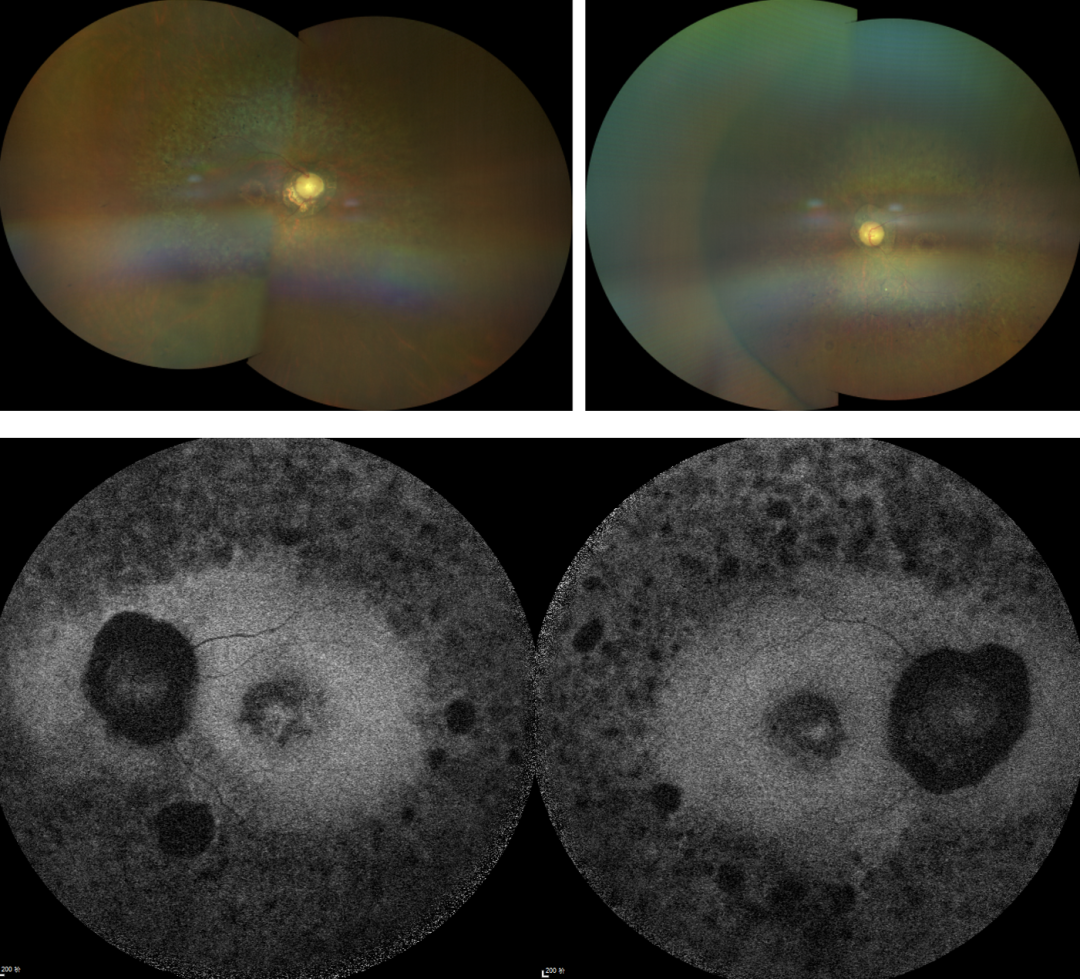

RP的診斷主要依靠眼底檢查、視野檢查、視網(wǎng)膜電圖(ERG)和基因檢測。眼底檢查可見典型的"骨細(xì)胞樣"色素沉著,ERG顯示視網(wǎng)膜功能下降,基因檢測可確定具體的突變基因。

視網(wǎng)膜色素變性